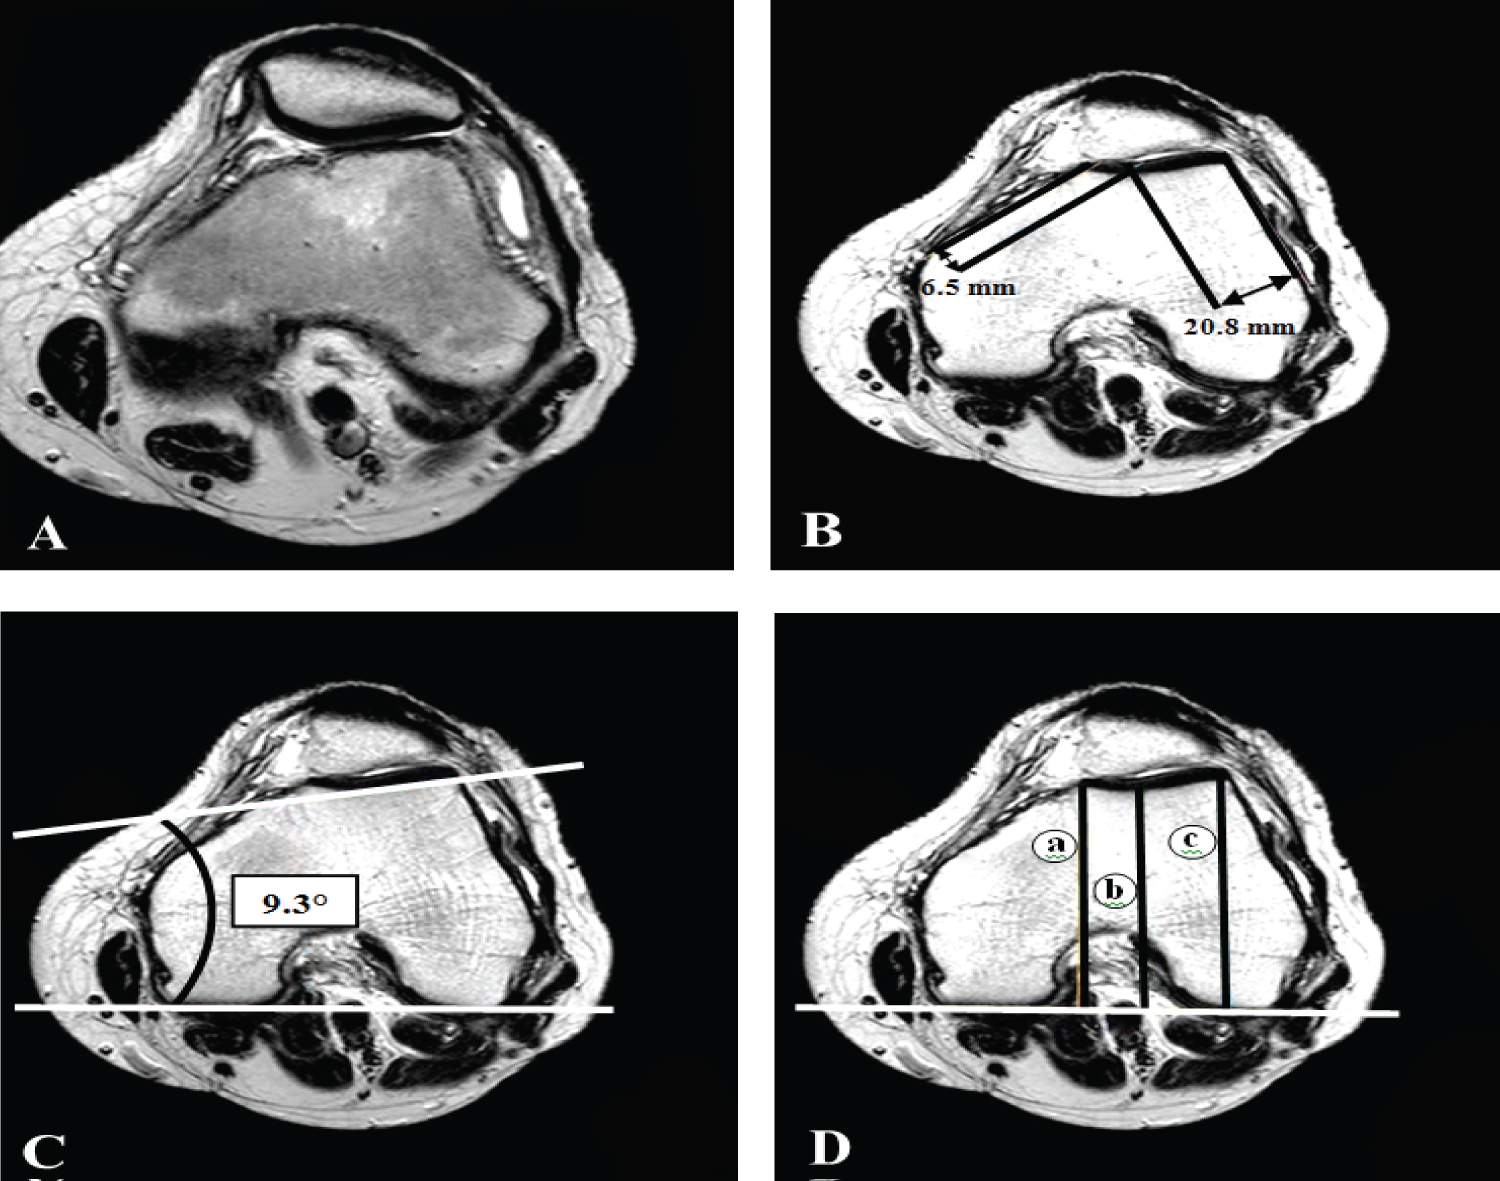

Figure 2: Axial T2 weighted images shows, A) Loss of contact between the patellofemoral joint surfaces laterally. B) Trochlear facet asymmetry 32% (normally not less than 40%), C) Lateral inclination angle 9.3° (normally not less than 11°), and D) Trochlear depth 1.7 mm (normally up to 3 mm), where a = 66.1 mm, b = 65.3 mm and c = 67.9 mm. View Figure 2